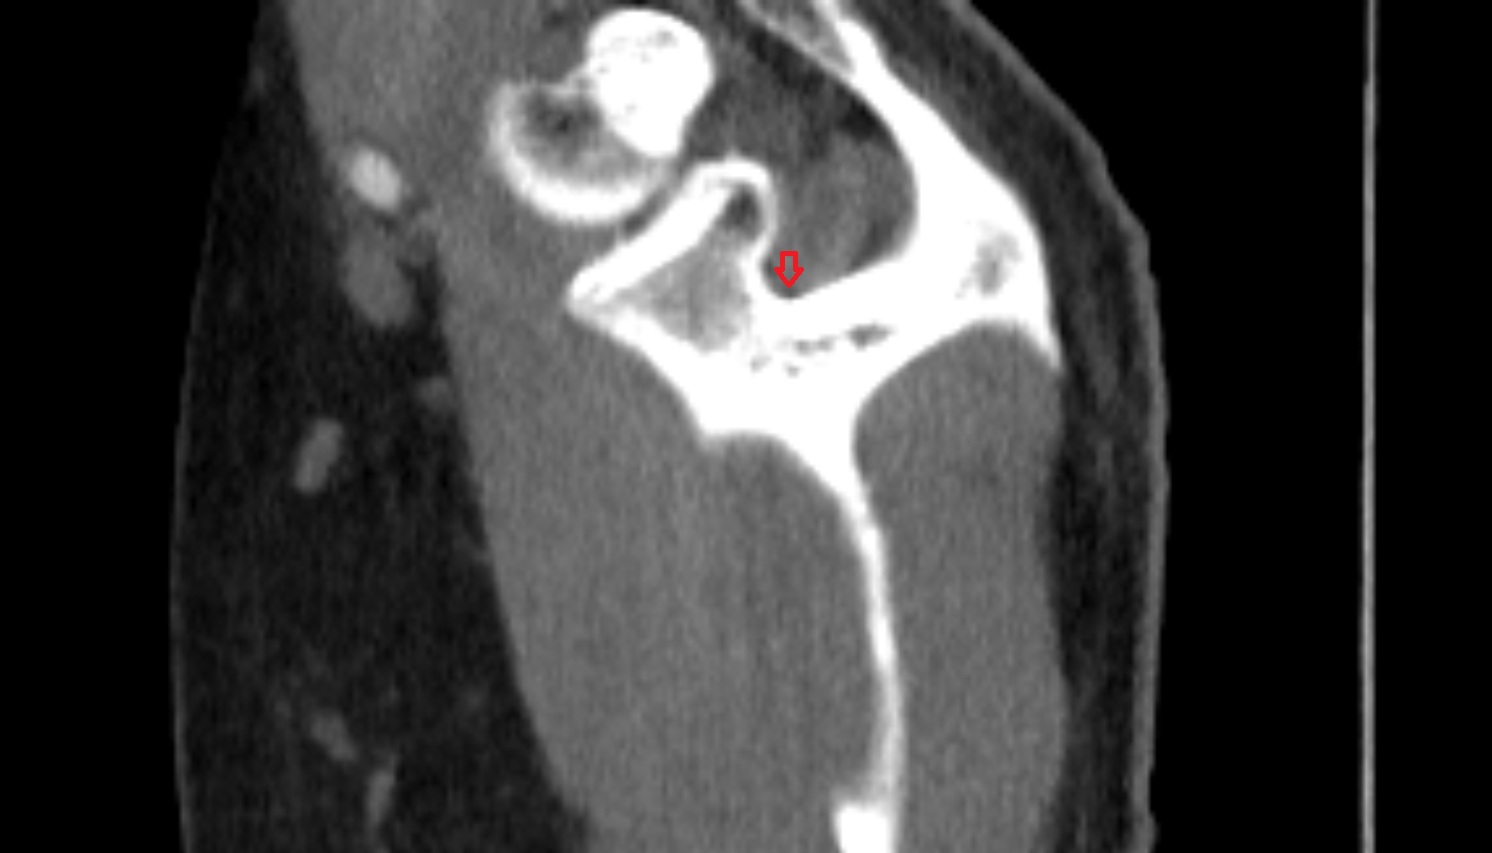

- Temporomandibular joint

- Mandibular condyle

- Mandibular fossa

- Articular disc of temporomandibular joint

- Articular eminence